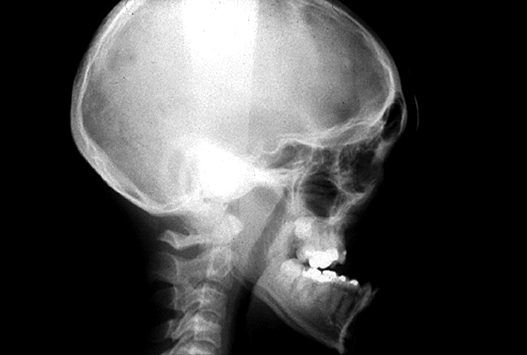

Figure 2: Demonstration of changes to posterior airway space by maxillary

advancement osteotomies. Preoperative (top) postoperative (bottom).

Orthognathic surgery is predominantly carried out for patients who are either skeletal class 2 or 3 and aims to achieve a class 1 relationship postoperatively and a good functioning occlusion. To achieve this, diagnosis of the underlying cause of the problem is performed by cephalometric analysis, which looks at the relationships of reproducible bony landmarks and angles on lateral cephalometric radiographs.

Diagnosis of the level of airway obstruction can be difficult and techniques including sleep nasendoscopy and apneoa graph can be employed. Lateral cephalometric radiographs can be helpful for assessing the posterior airway space and perhaps more accurately 3D CT analysis of the airway can be performed. Mandibular advancement devices when successful can be suggestive of airway obstruction at the level of the tongue base. It is our experience, however, that more severe OSA is usually a multi-level problem and success is more likely therefore with a multilevel solution.